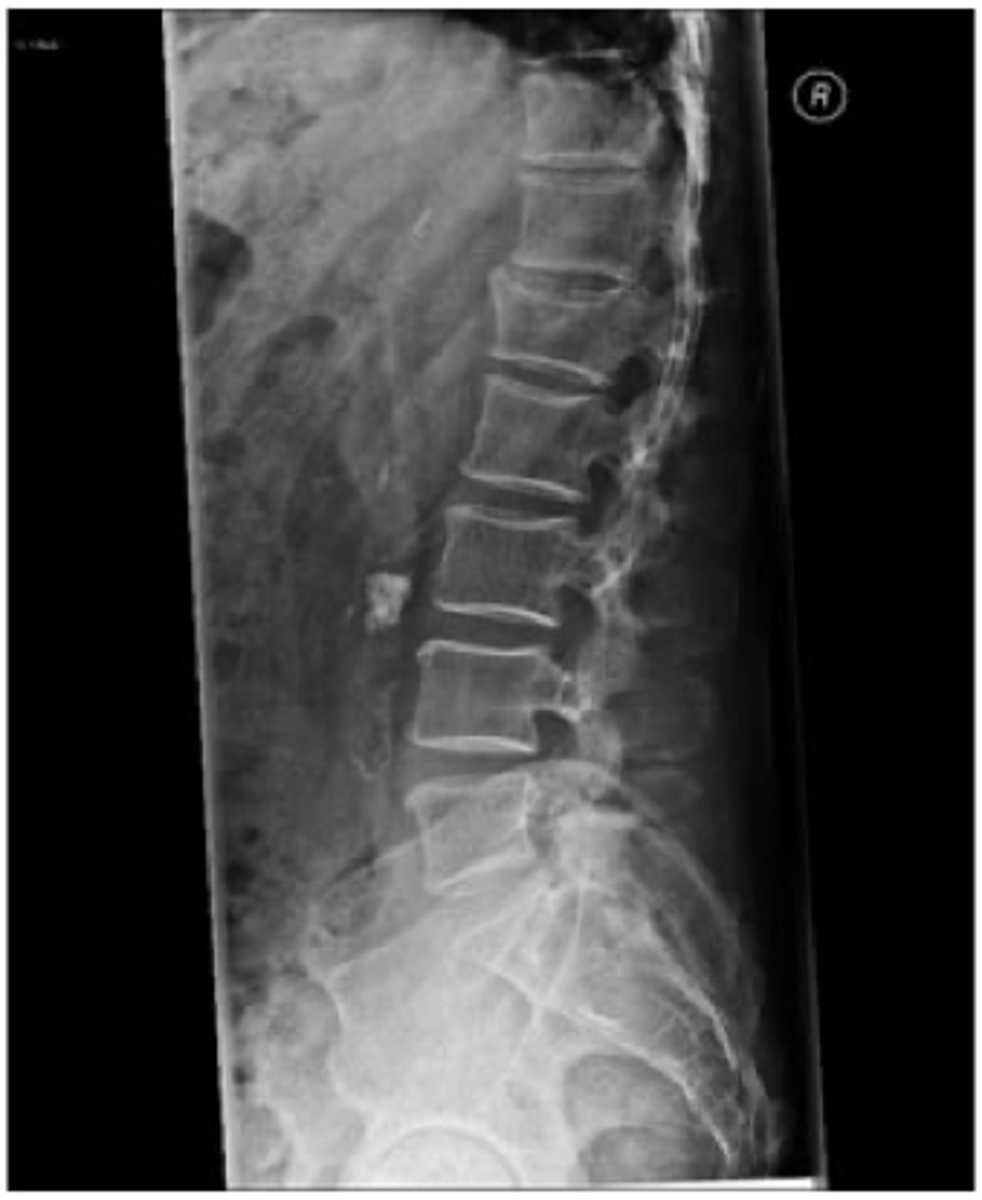

what does this x-ray show

osteoarthritis